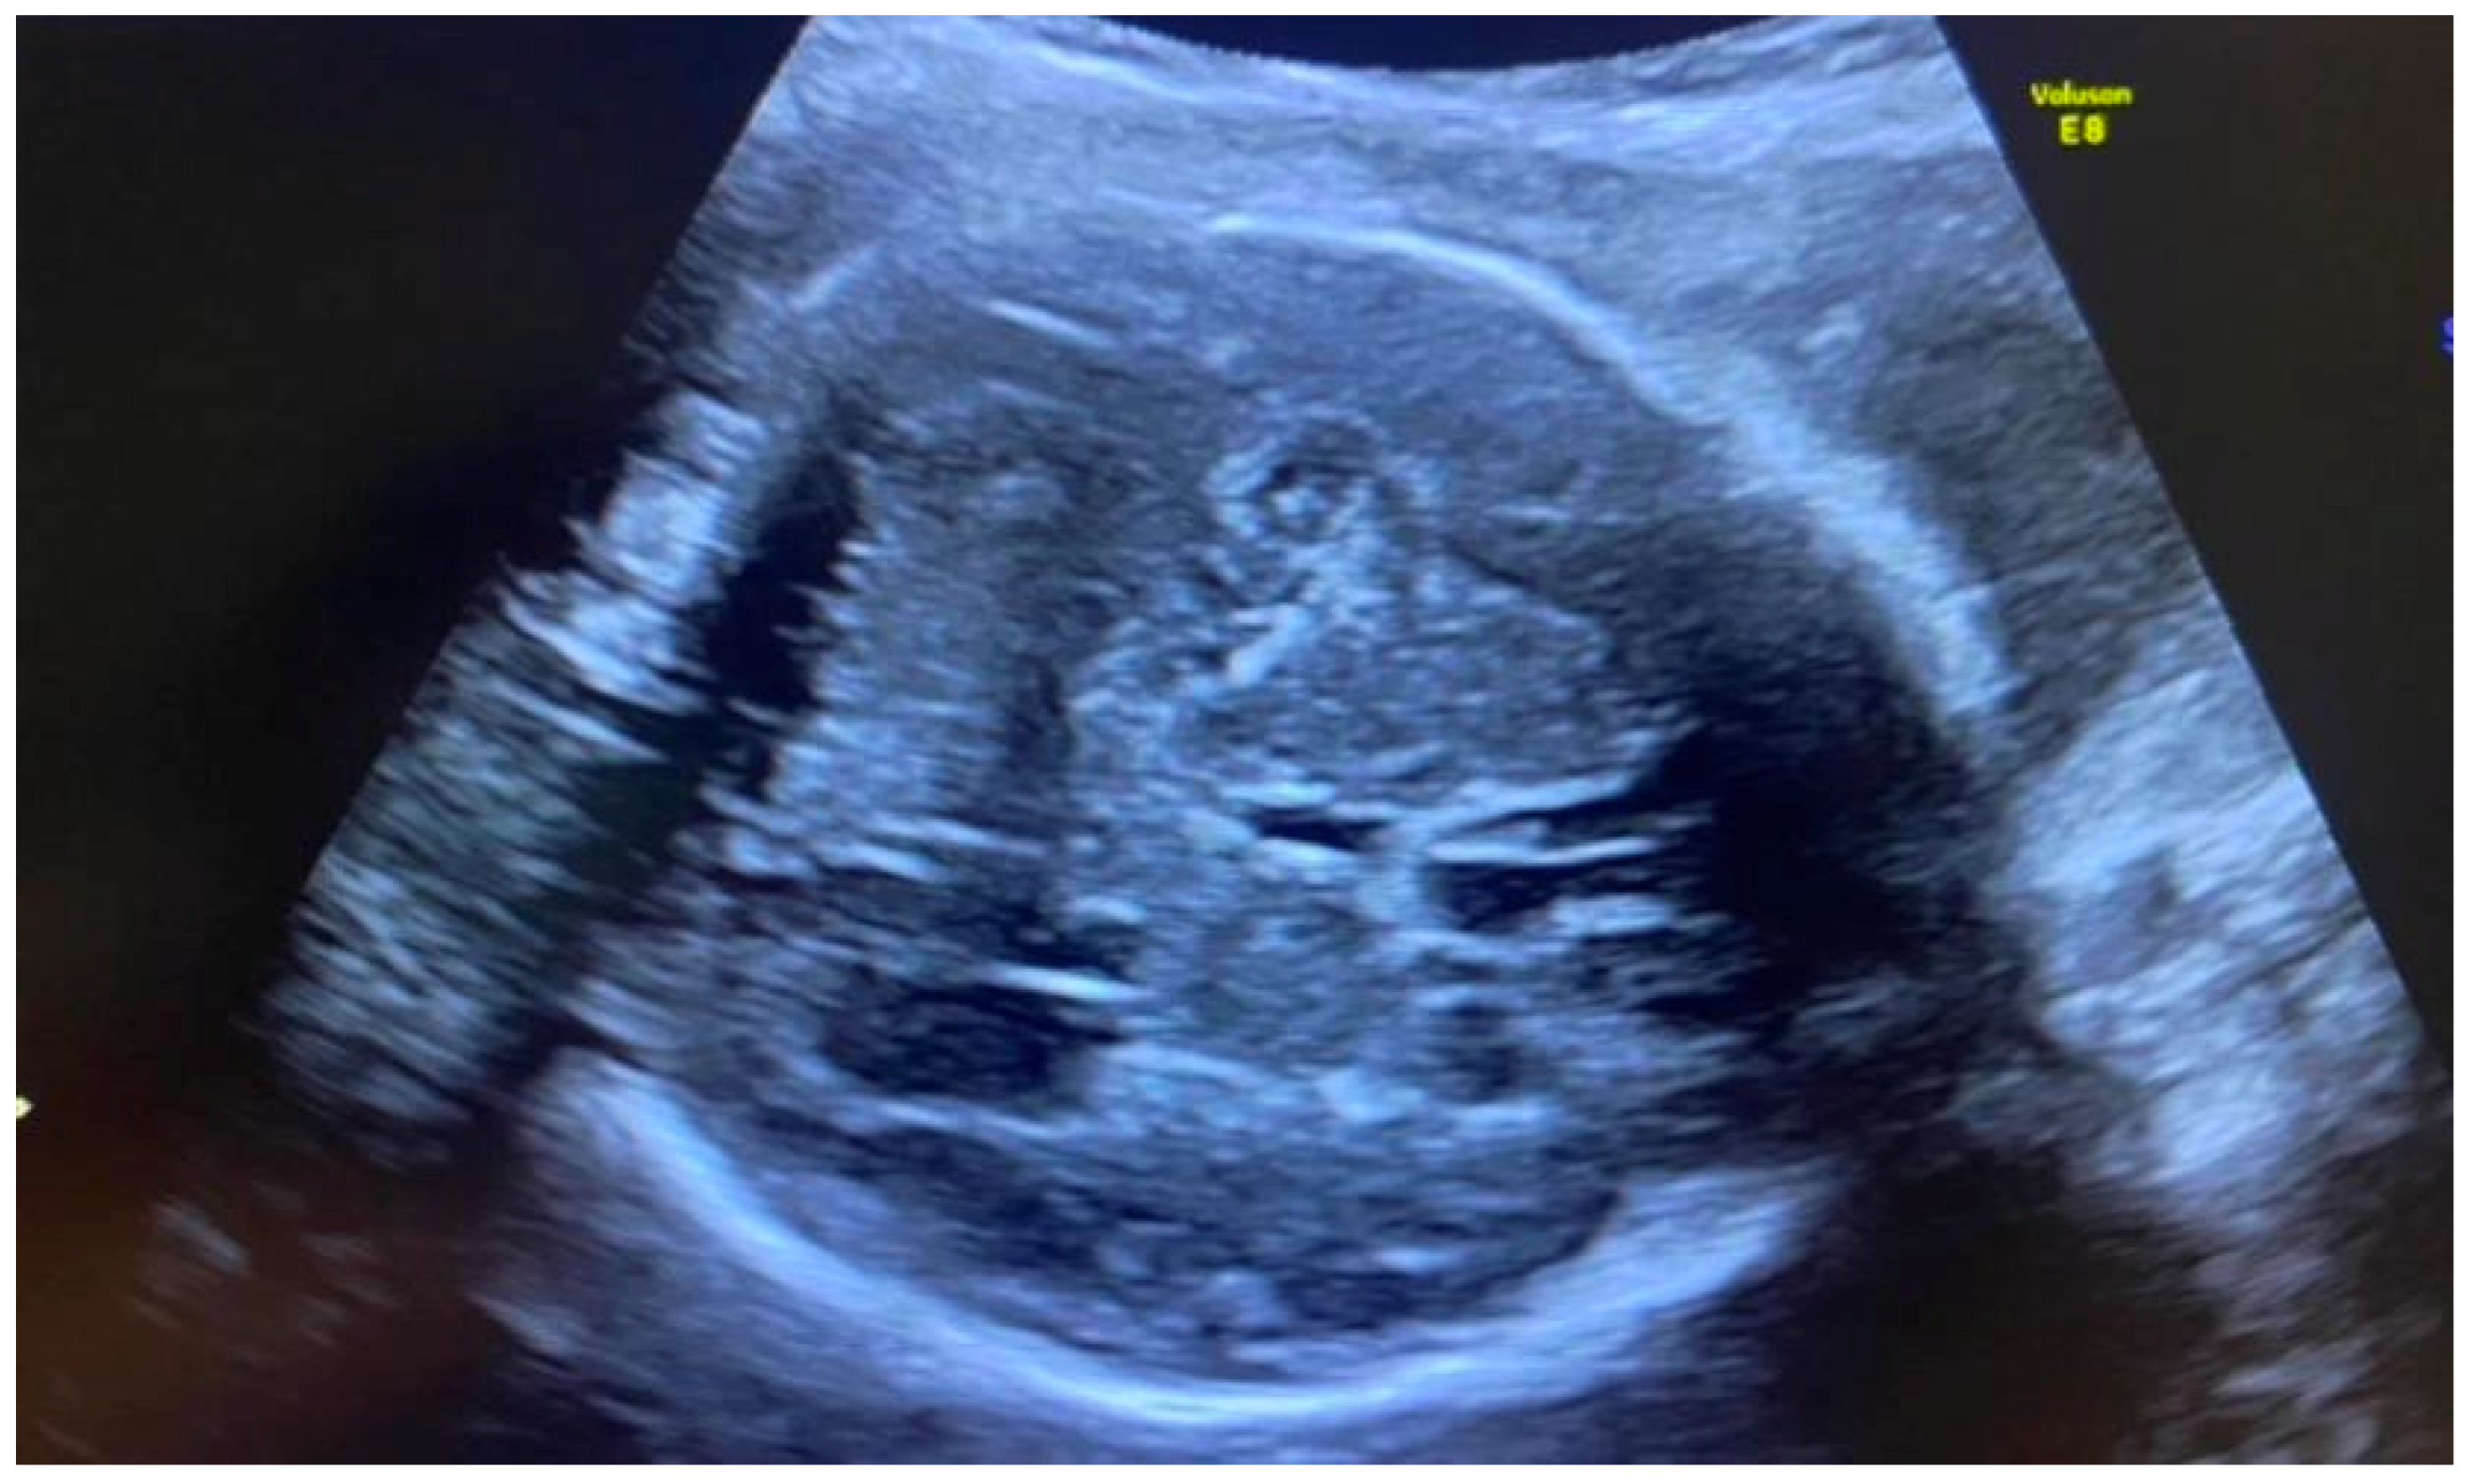

Congenital CMV fetal infection may be associated with a variety of CNS abnormalities. Those may be severe or mild; appear due to the early inflammatory, destructive, and obstructive processes of the brain infection; and directly influence fetal prognosis [60]. Ventriculomegaly (more than 15 mm), microcephaly (a decrease of less than two standard deviations), high echogenicity in the periventricular areas, and hydrocephaly may appear as severe intracranial signs. Increased cisterna magna (more than 8 mm), vermian hypoplasia, periventricular cysts, agenesis of the corpus callosum, lissencephaly, and porencephaly are often associated with congenital CMV infection [4,5,61]. Of these, ventriculomegaly and microcephaly are associated with the worst fetal prognosis. The mild cerebral findings related to fetal involvement include ventriculomegaly enlargement (10 to 15 mm) (Figure 3), intracranial calcifications (Figure 4), cysts of the choroid plexus, subependymal cysts, and intraventricular synechiae [62,63].

Figure 4. Intracranial calcifications; head circumference below the 3rd percentile—microcephaly.